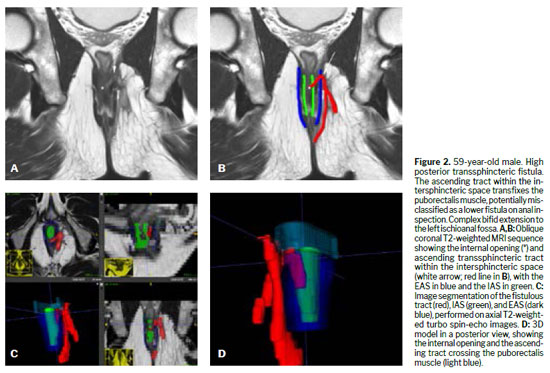

Various techniques can be used for the morphological evaluation of the fistula and its relationships with pelvic and perianal structures, including X-ray fistulography, computed tomography, endorectal or transrectal ultrasound, and MRI(11). Surgeons have access to 3D reconstructed endorectal ultrasound as a tool that can be used in the office and in outpatient settings, making it helpful in characterizing fistulas and anorectal abscesses, identifying the internal opening, and determining the main tract of a fistula. Among the various imaging modalities, MRI is the method of choice for studying anorectal fistulas, because it is superior for characterizing secondary tracts(2,6). Evidence from observational studies summarized in a narrative review has shown that MRI-guided surgery can reduce the likelihood of recurrence by approximately 75%, mainly by allowing precise preoperative identification of fistulous tracts and secondary extensions that might otherwise go undetected(5). Prospective observational studies suggest that this imaging method, used preoperatively, modifies surgical strategy in approximately 10% of patients with primary fistulas and 21% of those with primary, secondary, or Crohn’s disease-related fistulas(1). The benefits are even greater for sphincter-preserving procedures(5). Certain aspects of fistula morphology favor certain surgical procedures, whereas other procedures are contraindicated by specific morphological characteristics(7). Several studies have discussed which are the most relevant characteristics to be described in MRI reports in the evaluation of anorectal fistulas, as well as the best form of presentation, such as structured reporting, to improve understanding on the part of the attending physician(2,5,12). However, in cases of complex anorectal fistulas, reports can still be challenging to interpret for adequate surgical planning(3). In recent years, 3D modeling has gained space as a promising tool to aid in surgical planning(3). Figures 1–5 demonstrate MRI-based strategies in the evaluation of perianal fistulas, highlighting traditional 2D sequences as well as 3D reconstructions.

3D modelingOverviewIn the evaluation of perianal fistulas, 3D modeling from MRI data represents a novel and increasingly valuable adjunct. By translating conventional 2D sequences into interactive volumetric reconstructions, 3D models improve spatial understanding of complex fistulous anatomy, particularly regarding the relationship of tracts to the sphincter complex and pelvic floor structures. This enhanced visualization has been shown to facilitate communication between radiologists and surgeons, support multidisciplinary decision-making, and provide surgeons with a more intuitive roadmap for preoperative planning

(3,24,25).Notably, several studies have demonstrated that surgeons frequently reconsider the extent of disease or modify their operative strategy after reviewing 3D reconstructions in conjunction with standard MRI scans

Workflow and technical considerationsThe generation of 3D fistula models typically begins with a standard pelvic MRI protocol. The backbone of that protocol is composed of conventional high-resolution T2-weighted sequences in axial, coronal, and sagittal planes, often complemented by oblique sequences aligned with the anal canal. Some studies have incorporated isotropic 3D T2-weighted turbo spin-echo sequences, which provide thin-slice coverage and allow multiplanar reconstructions with no gaps

The 3D models illustrated in this review were generated from pelvic MRI datasets acquired in 1.5-T scanners, using the standard perianal fistula protocol of our institution. The imaging protocol included high-resolution T2-weighted turbo spin-echo sequences in the axial, coronal, and sagittal planes, supplemented by contrast-enhanced T1-weighted imaging. For complex fistulas, an additional isotropic 3D turbo-spin-echo T2-weighted sequence without fat suppression was obtained. After standard interpretation of the 2D MRI scans by an experienced abdominal radiologist, manual segmentation was performed on the sequence that best demonstrated the fistulous tract and anatomic landmarks—most often the oblique axial T2-weighted or the contrast-enhanced T1-weighted sequence. The Digital Imaging and Communications in Medicine (DICOM) datasets were imported into ITK-SNAP, version 4.4.0, open-source software validated for 3D medical image segmentation. Each relevant structure was segmented in a distinct color to optimize spatial comprehension by surgeons: the fistulous tract (red), the IAS (green), the puborectalis muscle (light blue), and the EAS (dark blue).

Clinical integrationAcross studies, the integration of 3D models into surgical planning has demonstrated several advantages. First, it improves diagnostic confidence, particularly in delineating secondary extensions, supralevator disease, and horseshoe fistulas